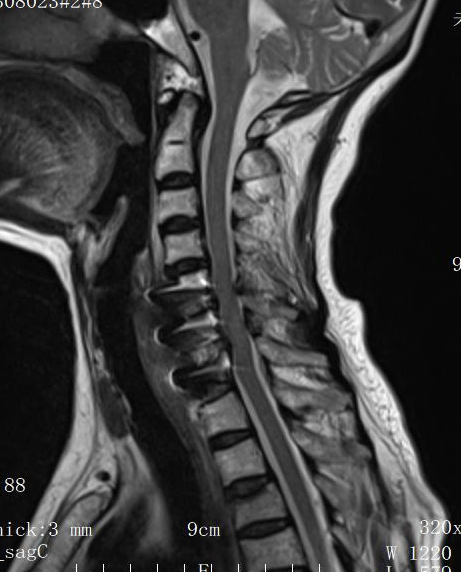

經(jīng)影像學(xué)檢查,確診為“頸7椎體骨折伴脊髓損傷”,且患者自身還患有糖尿病、高血壓等多種基礎(chǔ)疾病,身體機(jī)能及手術(shù)耐受性較差。

術(shù)后MRI